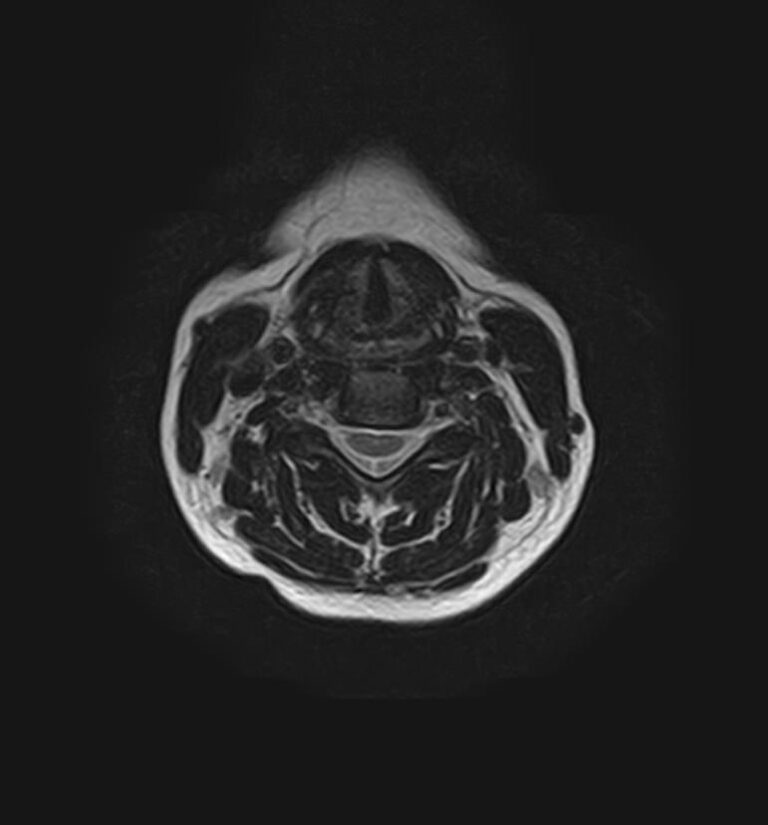

Сканирование проводится на современном высокопольном магнитно-резонансном томографе закрытого типа TOSHIBA VANTAGE TITAN 1,5 Тесла. Магнитно-резонансный томограф производит послойное сканирование исследуемой зоны в разных плоскостях, затем при помощи компьютерных программ преобразует полученные данные в трехмерные изображения с высокой степенью детализации.

Что показывает МРТ головного мозга + шейного отдела позвоночника

В рамках проведения данного комплексного исследования можно выявить:

• остеохондроз, спондилоартроз, спондилез, межпозвонковые грыжи, унковертебральный артроз, сколиоз, усиленный или выпрямленный лордоз как нарушение статической функции позвоночника, травмы, аномалии позвоночника.